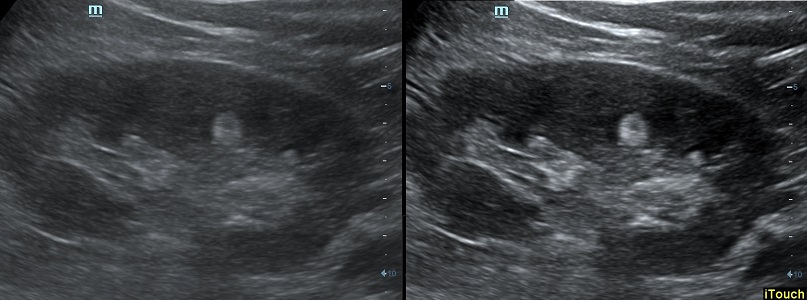

Оптимизация изображения происходит и за счет постобработки. Наиболее часто используемый инструмент - общее усиление (Gain). Усиление делает изображение «ярче», но чем сильнее усиление, тем меньше различия между структурами. Также используются усиление по времени (TGC) и усиление по длине (LGC), которые позволяют изменять отображение на экране послойно, позволяя подсветить гипоэхогенные участки, или, наоборот, снизить визуально эхогенность слишком ярких моментов. Данный вид оптимизации требует много времени, для упрощения работы доктора на приборах Mindray внедрена система автоматической оптимизации - iTouch.